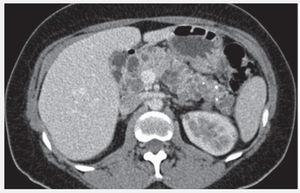

Figura 2. Quistes pancreáticos y renales.